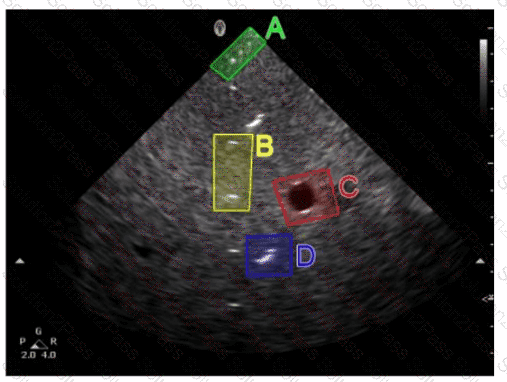

Which target group in this image of a tissue-mimicking phantom is used to evaluate axial resolution?

A.

Option A

B.

Option B

C.

Option C

D.

Option D